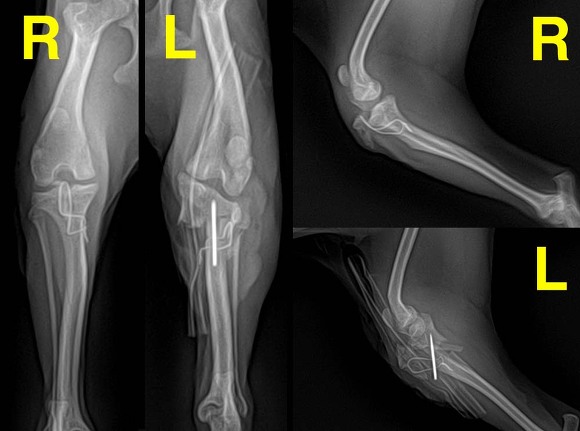

X-ray 상에서 슬개골탈구로 다리수술을 했다는

아이의 다리는 ‘슬개골탈구’, '골절'

전혀 설명도 없었던 '핀'까지 꽂혀있고

파주 모동물병원에서 슬개골수술 후

다리 염증이 잘 잡히지 않으면 “다리 절단”

염증이 잘 잡힌다하여도

무릎 위쪽 뼈를 절벽처럼 깎아놔

골절위험에 관절염을 달고 살아야 되며,

살과 근육, 인대도 녹고 피부도 괴사된 상태입니다.